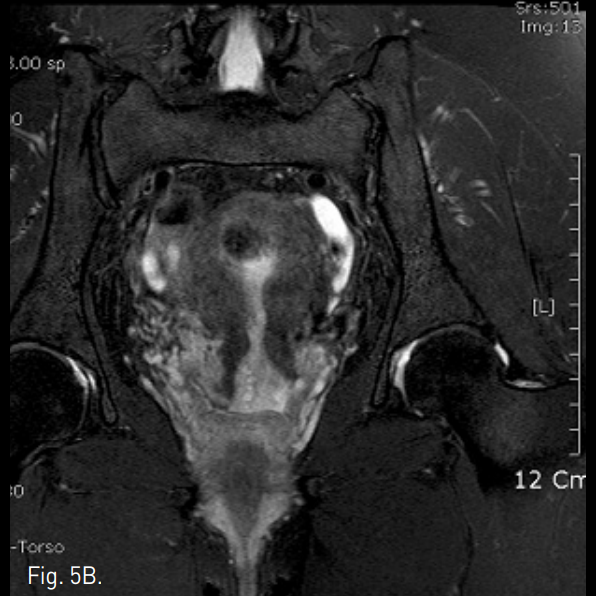

Fig. 5

A-C. One year follow-up T2-weighted transverse (A), coronal (B), sagittal (C) MR images show a small remnant of myoma with low signal intensity.

색전술 3개월 후 시행한 MRI에서 자궁근종의 크기가 최대직경 6.0cm에서 5.5cm로 감소하였고, intramural fiber가 모두 괴사된 것을 확인하였다(Fig. 4). 환자는 생리주기가 길어진 것 외에 다른 증상들은 보이지 않다가 약 6개월 후부터 생리주기 때 심한 하복부통과 생리혈의 증가를 호소하였고, endocavitary로 진단되어 자궁소파술을 2차례 시행받았다. 9개월 후 생리주간에 갑자기 덩어리를 동반한 다량의 출혈 경험을 호소하였고, 이후 환자의 생리기간의 증상이 완전히 소실되었다. 자궁동맥색전술 1년 후 추적 검사한 MRI에서 자궁근종 remnant만을 확인할 수 있었다(Fig. 5).